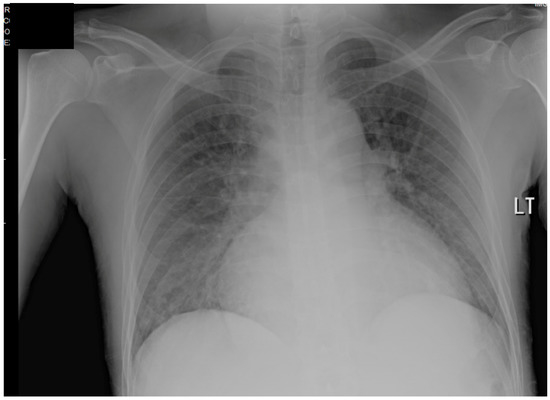

The patient’s EKG (Figure 1) on admission demonstrated a left bundle branch block pattern not previously documented in the patient’s medical history. Additionally, chest radiography (Figure 2) and computed tomography (Figure 3) on admission demonstrated cardiomegaly. Transthoracic echocardiography was technically difficult but demonstrated severe left ventricular systolic dysfunction with an ejection fraction of <15%. Initial brain natriuretic peptide (BNP) on admission was 981 pg/mL. The patient was recommended to start on 25 mg metoprolol succinate, 81 mg aspirin, 5 mg Lisinopril, and 40 mg atorvastatin. Metoprolol and Lisinopril were started initially as therapy for newly diagnosed DCM whereas aspirin and atorvastatin were started before coronary artery disease was ruled out with cardiac CT angiography (Figure 4 and Figure 5). The patient developed electrolyte abnormalities after the first day of treatment, including hypomagnesemia and hyperkalemia, likely secondary to longstanding untreated fluid overload due to heart failure. In response to this and the noted acute kidney injury, Lisinopril was discontinued. Additionally, the patient’s ALT and AST levels rose dramatically. Gastroenterology evaluation was obtained due to elevated liver function tests with a differential diagnosis of shock liver vs. Budd Chiari syndrome; therefore, N-Acetyl cysteine was prophylactically used and improved liver function over the subsequent week and atorvastatin was discontinued. The patient was continued on heart failure management. A repeat echocardiogram showed an improved ejection fraction of 25% with left ventricular dilation (left ventricular internal dimension in diastole 5.65 cm; left ventricular internal dimension in systole 4.95 cm; relative wall thickness 0.34; left ventricular mass 218.2 g; left ventricular mass index 131.8 g/m2) and no left ventricular thrombus noted. Additionally, mildly reduced right ventricular systolic function was noted.

Figure 2. Chest radiograph on admission, demonstrating cardiomegaly.